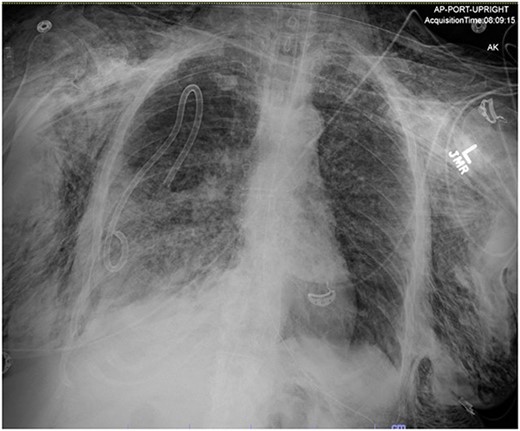

In the operating room (OR), the patient underwent intubation for TBNA using the Monarch® robotic bronchoscopy platform. Nine needle aspirations were obtained from the third-order RLL bronchi with each aliquot subjected to rapid on-site examination. While awaiting results, the patient developed retching, hemoptysis, bronchial bleeding from the superior segment of the RLL lobe and hypotension. The bleeding was managed with ice-cold saline and epinephrine. The patient required aggressive resuscitation with crystalloid, blood products and vasopressor therapy. She was transferred to the ICU where she remained intubated for ongoing resuscitation. In the ICU, the patient developed recurrent hypotension. Chest X-ray (CXR) revealed a right-sided pneumothorax (Fig. 1) that was treated with a small-bore pigtail chest tube and resulted in immediate improvement of her tension physiology. The pneumothorax resolved on repeat chest film while the patient remained intubated and sedated (Fig. 2).

AP upright chest radiograph showing placement of right-sided chest tube and resolution of right pneumothorax.